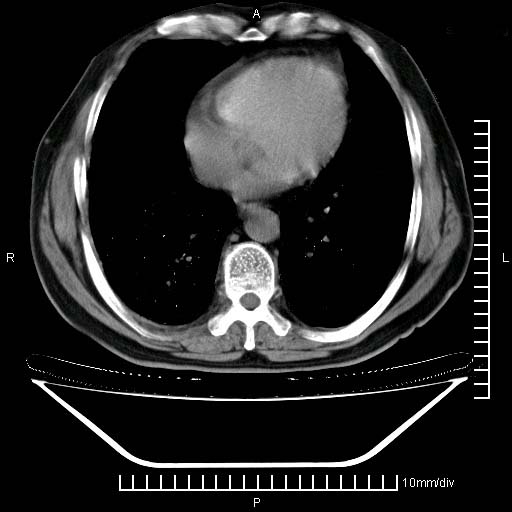

既往肺结核,近10几天,咳嗽,咳痰,右侧胸痛,疼痛较明显,右上肺斑块考虑结核灶胸膜粘连,增强,可惜动脉期没有定好,未见强化,可延迟4分后又见较明显强化,中心见低密度影,如果说结核是边缘强化,可这个灶强化的面积挺大的,让人很挠头。

1)两肺继发性肺结核。2)右侧胸膜增厚+少量胸腔积液。